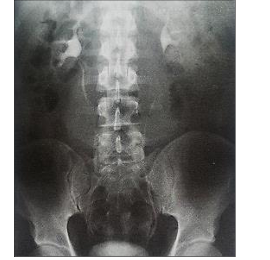

A radiografia representa um exame específico de abdômen com utilização de contraste:

De acordo com as informações, assinale a afirmativa correta.